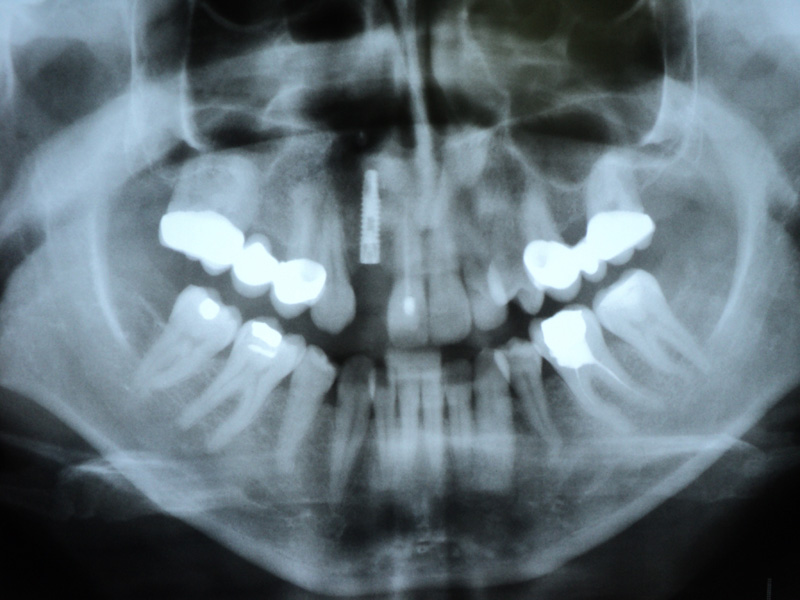

Implante - Galerie Foto

Caz IV